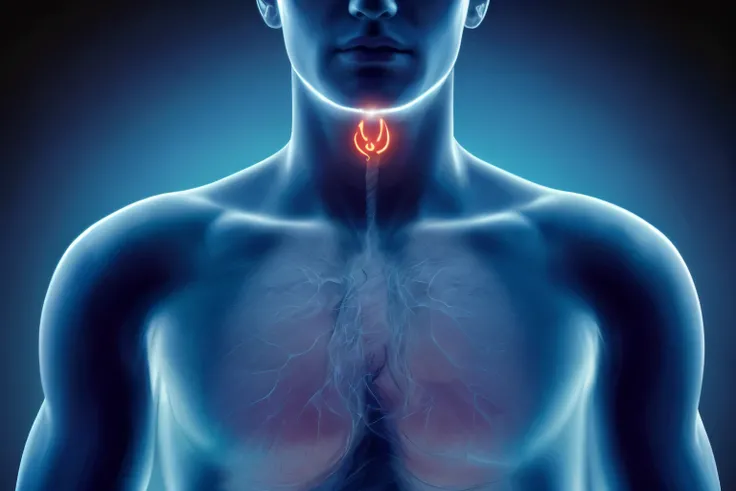

Pictures of swollen thyroid gland in neck, Use a Canon EOS 5D Mark IV with a 24

pictures of swollen thyroid gland in neck, Use a Canon EOS 5D Mark IV with a 24-70mm f/2.8 lens. Settings: ISO 100, aperture f/8, and shutter speed 1/125s to capture a sharp, vibrant image with a wide depth of field.

pictures of swollen thyroid gland in neck